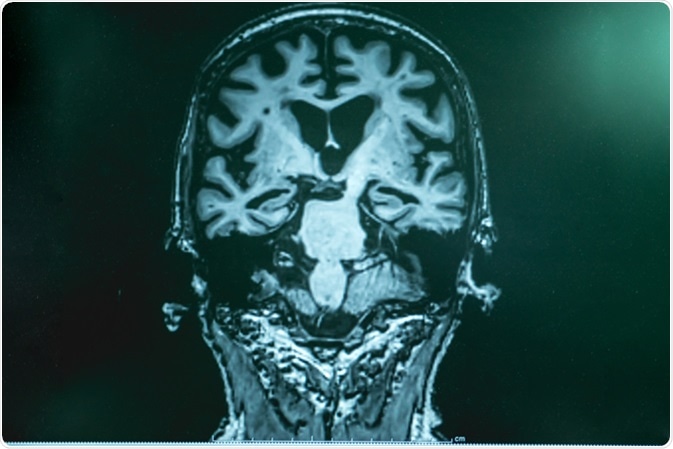

Alzheimer

Alzheimer's disease with MRI. Image Credit: Atthapon Raksthaput / Shutterstock